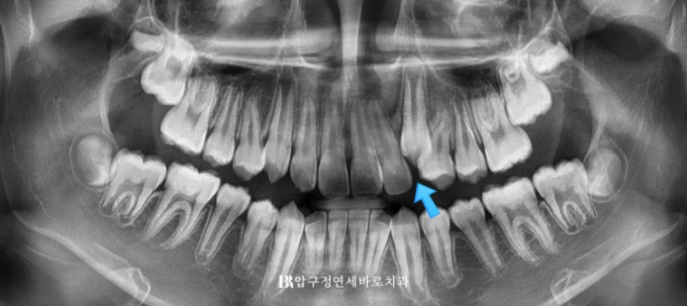

송곳니 덧니의 원인은 무엇일까요?

송곳니가 가장 마지막에 나오는 치아라서 먼저 나온 앞니에 자리를 빼앗긴 상태로 내려오게 됩니다.

즉 앞니 중 가장 늦게 내려오는 치아여서 이가 나올 공간이 부족한 상태가 되기 쉬우며 그래서 덧니가 되기 쉽습니다.